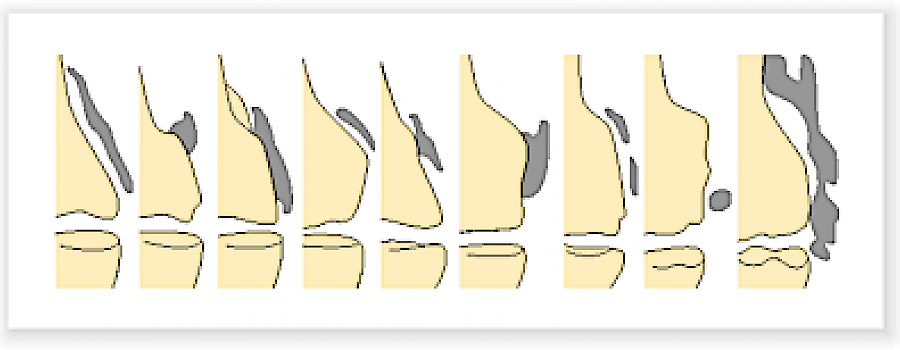

Der Stieda-Pellegrini-Köhler-Schatten ist eine Verknöcherung in den Weichteilen am inneren Femurepikondylus (im Sehnenansatz der Musculi adductor magnus oder gracilis oder im inneren Knieseitenband).